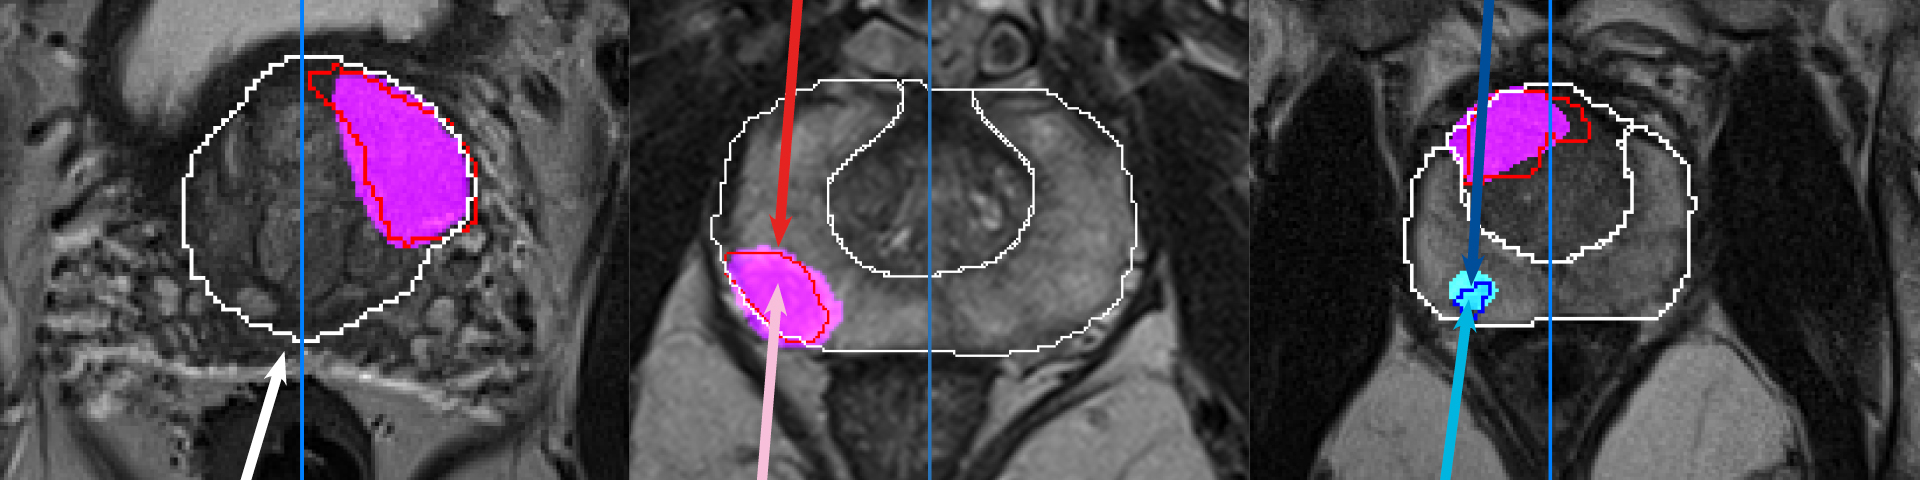

Beispielhaft wird „Prostate.Carcinoma.ai“ als erstes Produkt aus einer größeren zukünftigen Serie vom Kooperationspartner Mint Medical auf der RSNA vorgestellt. Integriert in die diagnostische Software mint LesionTM erkennt sie vollautomatisch die Prostata und markiert verdächtige Läsionen, wobei nach gutartigen und bösartigen Tumoren unterschieden wird. Die Bewertung der Läsionen und die anschließende Befundung liegt weiterhin in den Händen der Radiolog*innen.

Prostatakrebs ist die häufigste Krebserkrankung bei Männern in den westlichen Industriestaaten und nach Herz-Kreislauf-Erkrankungen deren zweithäufigste Todesursache. Allein in Deutschland erhalten nach Angaben der Deutschen Krebshilfe etwa 60.000 Männer jährlich die Diagnose Prostatakarzinom. Die radiologische Beurteilung von Prostata-Läsionen auf MRT-Aufnahmen ist höchst anspruchsvoll und von der Erfahrung der Radiolog*innen abhängig. Der Einsatz von Künstlicher Intelligenz (KI) kann dabei helfen, die Genauigkeit von Diagnosen sicherzustellen und gleichzeitig die Befundungszeit erheblich zu verkürzen.